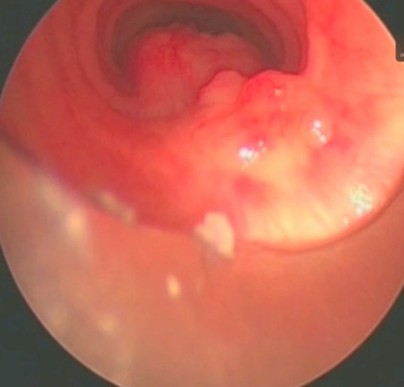

Ασθενής 56 ετών με καρκίνο μαστού και δυστυχώς υποτροπή σε λεμφαδένες με πίεση και διήθηση της τραχείας. Σε αυτήν την περίπτωση η θεραπεία είναι παρηγορητική και αποσκοπεί στο να προσφέρει ποιότητα ζωής χωρίς να επιτυγχάνει ίαση του προβλήματος.

Η διάνοιξη διενεργήθηκε με ίνες laser.

Η πρώτη φωτογραφία δείχνει το σημείο των λεμφαδένων που έχουν περάσει στην τραχεία, η δεύτερη την εξαέρωση με laser και η τρίτη την ανοιχτή τραχεία αφού οι λεμφαδένες έχουν εξαερωθεί.